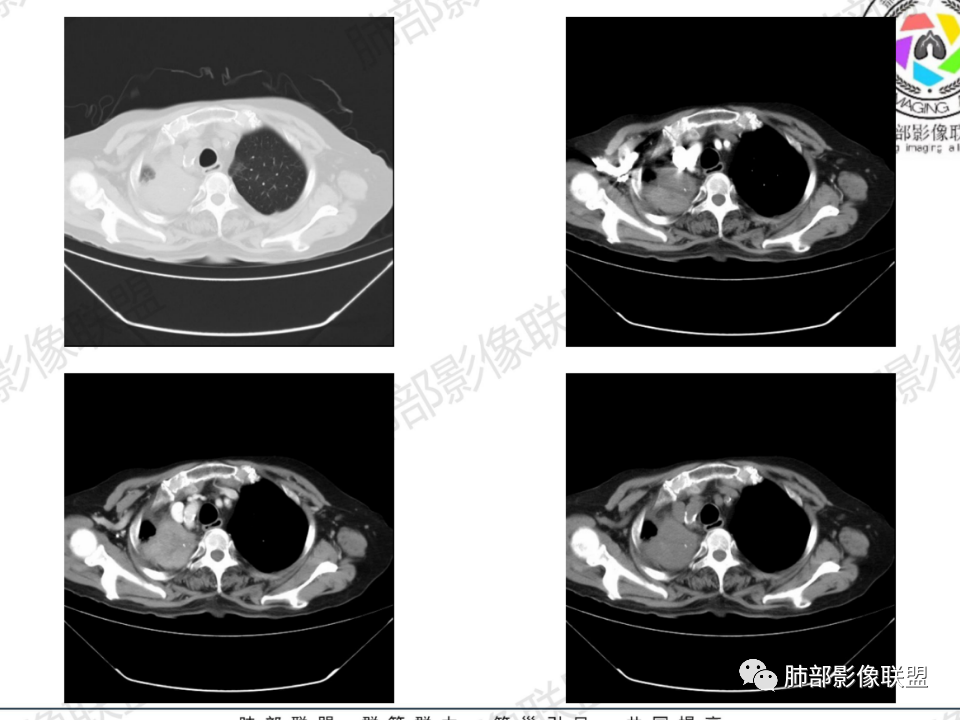

老年患者,病程中等,有咳嗽/喘息/低热症状,肿瘤标志物升高,感染标志物不高,右上肺新生物,中央型,边界清楚,有分叶,支气管截断,内有坏死,不均匀强化,考虑肺癌,鳞癌?

那个人:老年女性,亚急性病程,咳嗽发热。有垂体前叶功能减退,目前激素替代治疗,长期激素,量小,不知道累积量,没有目前激素水平指标。既往有淋巴结结核病史。肿瘤标记物Ca125升高。血沉升高,C反应蛋白轻度异常。影像,右肺上叶靠近肺门团块影,右肺门淋巴结钙化肿大,支气管狭窄,局部增厚,团块影外朝内改变,强化明显,血管破坏不明显,有粘液。和纵隔胸膜分界清楚,周围肺组织有斑片渗出影,右侧胸腔积液,考虑炎性?结核?支气管镜检查除外恶性飞鹰行动:老年患者,影像表现 右肺上叶占位性病变,边界清楚,有分叶征,内见细小钙化,右肺上叶支气管截断,增强病灶不均匀强化,病灶内有条状坏死区(扩张的支气管?),纵膈内未见增大淋巴结,考虑炎性病变,结核可能。一切∮随缘:右肺上叶实性肿块形态不规则,呈三角形,边缘分叶,边界伴有磨玻璃影,近段支气管未见明显显示,可能堵塞,病变平扫密度均匀,增强后可见低密度坏死无强化,周围略强化,右肺下叶散在结节。心包积液,及右侧胸腔积液,临床:有低热,低蛋白血症,肿瘤标记物高,考虑恶性:腺癌,神经内分泌癌(强化偏弱了),淋巴瘤,鉴别:结核红星:老年女性患者右肺上叶,肺门上区 分叶状肿块 ,右肺上叶支气管显示不清,增强扫描肿块,中等程度强化可见小斑片状坏死区,病灶内部可见斑点状钙化灶,病灶周围可见斑片状及小斑点状影,纵膈淋巴结增大,其他区域,胸膜下可见斑点状钙化。考虑肉芽肿性病变,结核的可能性大。老年患者最排除肿瘤性病变腺癌。土娃:右上肺不规则肿块影,边缘分叶,边界磨玻璃影欠清,病灶分叉状,内见点状钙化影及坏死灶,支气管堵塞,病灶增强强化不明显。考虑瘤样结核,鉴别淋巴瘤。张小兵:老年女性,亚急性病程,右肺上叶见不规则肿块,边缘平直凹陷为主,周围GGO边界不清,内见点状钙化及坏死灶,增强持续性渐进强化,右侧少量胸腔积液,双肺门及纵隔肿大淋巴结伴钙化,综合考虑慢性炎症。saf:老年患者,影像表现 右肺上叶占位性病变,边界清楚,有分叶征,增强病灶明显不均匀强化,纵膈内未见增大淋巴结,考虑炎性病变,结核可能。小兜:老年女性,咳嗽喘息一月,发热三天,肿瘤标志物升高,长期激素替代治疗。CT示右肺上叶近肺门不规则实变影,周围伴磨玻璃影,增强持续性渐进强化,内部血管破坏不厉害,内部可见多发条形低密度灶,右侧胸腔可见少量积液,双肺门及纵隔可见钙化淋巴结,考虑为炎性病变,结核可能玫:女,79咳嗽,喘息一月,发热三天入院,右肺上叶不规则形软组织密度肿块影,边界清晰,边缘见分叶及细短毛刺,病灶内见点状钙化影及稍低密度区,病灶边缘呈磨玻璃样改变,增强扫描,病灶呈不均匀性强化,考虑炎性病变,鉴别鳞癌。大雄:老年女性,既往诊断淋巴结结核,提示已治愈,近2年服用激素,诱导结核复燃→发热;纵隔肺门淋巴结肿大钙化,压迫支气管,右肺上中下叶支气管均狭窄→喘息咳嗽;尖段支气管受累闭塞→肺不张、支气管粘液栓;累及胸膜,结核性胸膜炎并胸水→右侧胸痛;实验室,血沉快,CA125高,低蛋白,符合;下一步,支气管镜尖段支气管刷检抗酸染色周太狼:老年女性,亚急性病程,肿瘤标志物升高。CT示右肺上叶尖段不规则肿块影,有分叶、收缩,周围伴磨玻璃影,增强渐进强化,内部可见多发条形低密度灶,右侧胸腔及心包少量积液,纵隔内淋巴结稍增大。倾向于恶性病变,肺癌伴阻塞性炎变可能。丽:老年女性,右肺上叶不规则软组织肿块,边缘清晰,内密度不均,可见点状钙化及粘液栓,周围可见片状高密度影,增强后均匀强化,内多发低密度,纵膈多发钙化淋巴结,考虑结核可能大,建议结合支气管镜检查除外肿瘤宇宙:右胸廓缩小,右肺上叶团块影及不张,平直边,周围磨玻璃影,纤细胸膜牵拉,上叶尖段支气管堵塞,明显延迟强化,可见支气管粘液栓,两肺门钙化淋巴结,右侧胸水,考性炎性肉芽肿,鉴别腺癌王秀仙:右肺上叶肺门区肿块,上叶支气管开口阻塞,形态不规则,密度不均,内可见支气管粘液栓及多发小灶性坏死,周围磨玻璃影边缘模糊,渐进强化,右侧胸腔积液、胸膜钙化,考虑炎性肉芽肿性病变,慢性炎症。鉴别鳞癌,结核。刘丹:老年女性,右肺上叶肿块伴钙化,右肺上叶支气管截断,增强后均匀强化,周边可见点片状模糊影,右侧胸腔积液,右肺门淋巴结增大,考虑占位并阻塞性炎症,肿瘤?结核?建议纤支镜检查。小飞:右肺上叶纵隔旁软组织肿块,边缘深分叶、长毛刺及毛刷样短毛刺,边缘磨玻璃影,磨玻璃边界模糊,支气管截断,平扫密度不均,可见点状钙化,增强不均匀明显强化,心影增大,心包积液,右侧胸腔积液,考虑恶性肿瘤,腺癌?秦化君:右肺上叶不规则分叶软组织密度肿块,边缘清晰,胸膜牵拉,周围花花草草,上叶尖段支气管阻塞,内可见点状钙化,增强后密度不均可见支气管粘液栓及坏死区,内见血管分枝。中间段及中叶,下叶支气管狭窄,壁见钙化。右肺门淋巴结肿大,右侧胸腔积液,心包粘连肥厚。考虑1右上肺恶性病变,鳞癌?2右肺多叶段支气管狭窄,考虑支气管内膜结核?3胸腔积液及肺门淋巴结肿大,转移?风儿:老年女性,右肺上叶肿块,形态不规则,外围大内带小,边缘分叶膨隆平直及毛糙,密度不均,内见支气管粘液栓及多发小灶性坏死,坏死边缘清晰 ,渐进强化,上叶尖段支气管阻塞,叶支气管壁有局限性增厚,邻近胸膜腔微积液;纵隔及双肺门淋巴结肿大,部分钙化,右侧胸腔积液、心包积液、胸膜钙化,考虑炎性,肉芽肿性结核可能性大。鉴别鳞癌,女性及血供均不支持;腺癌,坏死边界太清晰。流心明智:老年女性,79岁,咳嗽、气短1月,发热3天。胸CT:右肺上叶见不规则肿块,边缘有膨隆、有平直凹陷,周围GGO边界不清,病灶内见点状钙化、粘液栓,尖段支气管未见,增强持续性渐进强化,右侧少量胸腔积液,双肺门及纵隔肿大淋巴结伴钙化,肺动脉增粗。考虑:右上叶尖段堵塞并慢性炎症,支气管TB并结石?鉴别Ca

右肺体积小,提示既往结核

支气管影

前,后段都在,没有堵塞

支气管壁增厚,周围磨玻璃边界不清,提示炎症。胸膜下钙化符合结核

近期发热符合感染

这个层面往上应该是尖段,显示不清

背段支气管周围增厚伴钙化,符合结核改变

胸腔积液并胸膜钙化,符合结核;

结核是肯定有。现在最大问题是尖段

近端显示不清,但是远端是粘液栓,可以认为是还行的

如果是近端鳞癌,远端应该会堵塞,不会整个肿块里面还有较为通畅的支气管

这个区域我们看到密度与周围一致,并不是肺癌伴周围不张的感觉,所以鳞癌暂时是不支持的

临床信息:老年女性,亚急性病程,咳嗽发热。有激素使用史。既往有淋巴结结核病史。肿瘤标记物Ca125升高。血沉升高,C反应蛋白轻度异常。 影像所见:右侧胸廓相对狭小,右肺上叶不规则团块影贴附纵隔旁,轻度分叶,整体密度较均匀,偶见钙点。

相应上叶尖端及前段支气管开口未能追踪(阻塞),开口处见钙化。病灶渐进性强化,并衬托出较完整尖段及前段含液支气管影。支气管开口区域未见异常高密度强化(如类癌等)及相对乏血供区(如鳞癌)。病灶区未见液化坏死。右上纵隔及胸廓入口区未见病灶胸膜外突破(栽赃)。

右肺上叶后段等区域散在片状影,边界不清(提示渗出性病灶)。

纵隔及双肺门见钙化淋巴结。心包积液,右侧胸腔积液(提示存在活动新病灶)。双侧胸膜下见多发斑点状钙化,胸廓变形(提示存在结核基础病变可能)。 诊断意见:综上,右肺上叶块状影更符合继发性肺结核。 最后小结:既往诊断淋巴结结核,提示已治愈。近2年服用激素,可疑诱导结核复燃,也可引起发热。纵隔肺门淋巴结肿大钙化,压迫支气管,右肺上中下叶支气管均狭窄,所以引起喘息咳嗽。尖段支气管受累闭塞,导致肺不张、支气管粘液栓,出现条状无强化区。病变累及胸膜,导致结核性胸膜炎并胸水,引起右侧胸痛。实验室检查血沉快,CA125高,低蛋白,均符合结核。下一步,建议支气管镜尖段支气管刷检并抗酸染色。(本段摘自於雄老师精彩发言)